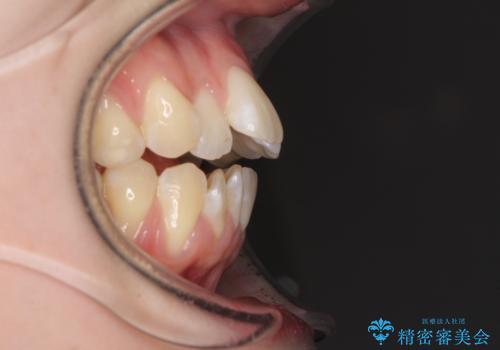

気になるデコボコとオープンバイト インビザラインでの矯正治療

- 前歯のデコボコと上下が開いていることを気にして来院された患者様です。

いわゆるオープンバイトは、インビザラインによる治療が適しているため、インビザラインにて治療を行うこととしました。